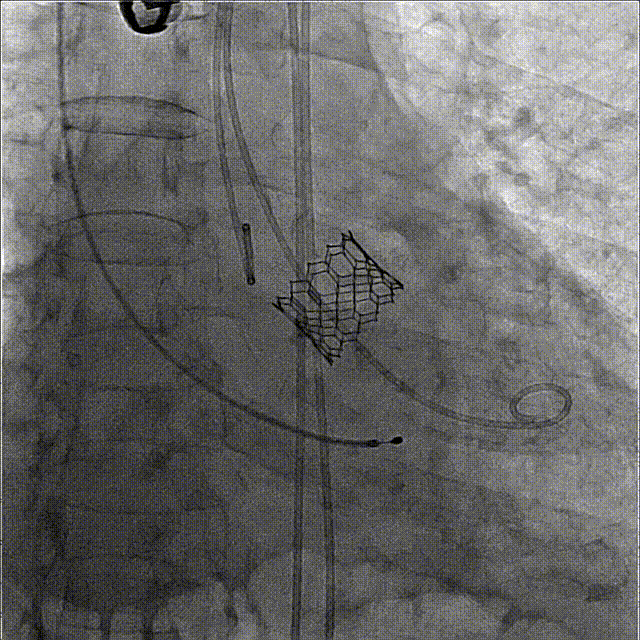

6、造影确定瓣膜到位,180bpm快速起搏下精准释放瓣膜;

7、撤出输送系统,根部造影结果显示瓣膜释放后形态位置良好、无瓣周漏,且左右冠脉均显影正常,冠脉血流未受影响;